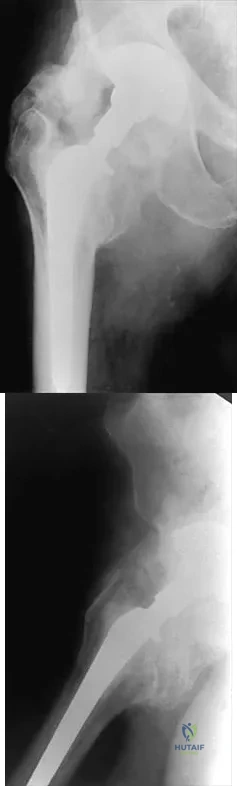

Question 53

A 14-year-old boy sustained a femoral neck fracture in a fall from a tree and underwent open reduction and internal fixation 6 months ago. Follow-up examination now reveals an antalgic Trendelenburg gait and painful range of motion. A radiograph is shown in Figure 23, and a CT scan shows a nonunion. Treatment should consist of

Explanation